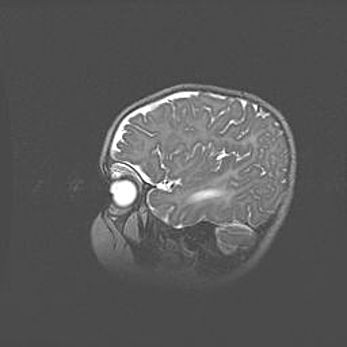

Подострая гематома правой гемисферы мозжечка.

Наружная гидроцефалия.

Возраст: 15 дней

Вес: 3100 г

Пол: женский

Окружность головы: 37 см

Срок гестации: 35-36 недель

При открытой наружной форме гидроцефалии у новорожденных расширяются и переполняются субарахноидные пространства.

Кровоизлияния в мозжечок имеют две клинико-анатомические формы: полушарные гематомы и кровоизлияния в червь.

К появлению этой патологии может привести: повреждения головного мозга, возникающие в результате асфиксии и гипоксии плода при беременности, или травмы во время родов. Редко гематома мозжечка может быть результатом первичной коагулопатии и сосудистой мальформации, диссеминированном внутрисосудистом свертывании, изоиммунной тромбоцитопении.